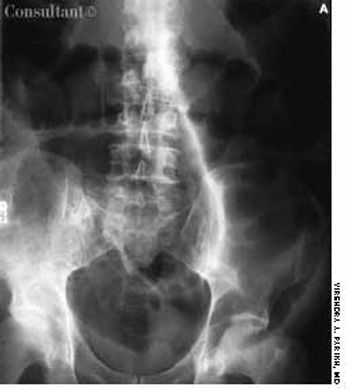

Endoscopic evaluation of a 61-year-old man hospitalized with a 4-month history of rectal bleeding, mucous discharge, and change in bowel habits revealed this large, sessile villous adenoma. The lesion occupied half the circumference of the bowel wall in the distal sigmoid colon, 25 cm from the anal verge. Examination of biopsy specimens showed benign villoglandular adenoma with atypia, with no invasive carcinoma. Sigmoid resection was carried out, and the patient recovered well.